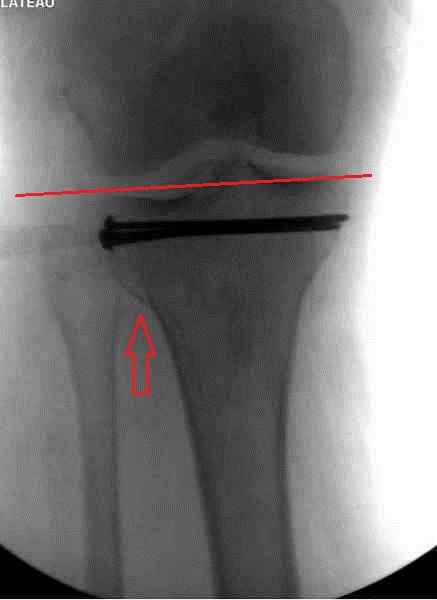

Как всегда прекрасная презентация. Совершенно согласен с необходимостью сохранять мениск и вообще согласен со всем, кроме одного. Фиксация должна проводиться после правильно выполненной репозиции. Главная цель репозиции - это восстановить высоту наружного мыщелка. В норме наружный мыщелок выше внутреннего на 4-5 мм на снимке в переднее заднем направлении АР.

Необходимость репозиции возникает при снижении высоты от 3 до 5 мм по разным источникам. По моему опыту 4 мм. Если не восстановить высоту мыщелка возникает вальгизация коленного сустава с относительным расслаблением передней крестообразной связки. При этом развивается нестабильность коленного сустава из-за недостаточности ПКС.

По этому если фрагмент большой есть необходимость репозиции дистального угла и фиксация пластинкой против соскальзывания ANTIGLIDING PLATE. Если перелом фрагментарный? то очень помогают описанные субхондральные шурупы RAFT, но

чтобы сохранить высоту суставной площадки шурупы одним концом должны опираться на пластинку а другим - на кортекс по внутренней стороне. Идеально сочетание ANTIGLIDING BUTRESS PLATE + RAFT SCREWS.

На представленном после операционном снимке нет репозиции, на что указывает низкое положение тибиального плато и перекрытие кортикальных пластинок в метафизарной части - указано стрелкой. Обычно чрескожную фиксацию я применяю

при переломе без депрессии отломка, или если после СТ понятно, что можно сделать закрытую репозицию, то шуруп с шайбой можно установить прямо в угол, что предотвращает скольжение отломка.